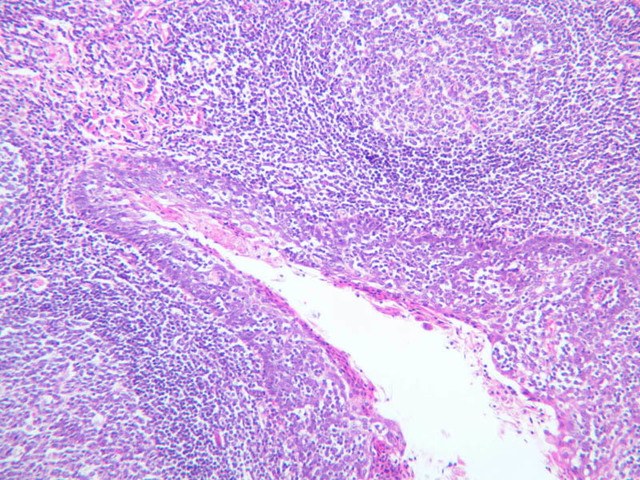

Lymph Nodes

When foreign substances or antigens get into body tissues, such materials are usually taken into the lymph and transported to aggregations of lymphoid tissue called lymph nodes (slide A-32, H&E [2.5x-labeled, 10x, 20x, 40x] [2.5x-labeled, 10x, 20x] [2.5x, 10x, 20x-labeled, 40x]; A-33, H&E [2.5x, 10x, 20x, 40x]; A-34, retic [2.5x, 10x, 20x, 40x-labeled]; A-35, H&E [2.5x, 10x, 20x, 40x]), which are composed of lymph nodules invested by a distinct connective tissue capsule. The node is visibly separable into a cortex, where the densely stained nodules are concentrated, and a light staining medulla (A-32 [2.5x, 10x-labeled, 20x, 40x]). Strands, or trabeculae, of connective tissue separate the node into cortical compartments and join centrally in the node to emerge at the indented side known as the hilus. Small arteries and veins enter and leave the node at the hilus, being distributed in the node through the trabeculae. Capillary branches from the arteries are spread throughout the lymphoid node. Multiple afferent lymphatic vessels penetrate the capsule of the node, emptying into a subcapsular sinus which is a relatively cell-free zone (A-32 [2.5x, 10x, 20x, 40x-labeled]). Unidirectional flow of lymph from the afferent lymphatics into the sinus is assured by the valves in the vessels. From the subcapsular sinuses, lymph percolates through the relatively unobstructed cortical sinuses to the medulla. During this flow the lymph is filtered by phagocytes and foreign antigens are presented to lymphocytes by dendritic cells, the resident antigenpresenting cells. Nodules are formed as needed and subsequently disappear. Lymph finally reaches the medullary sinuses bounded by wide cords of tissue and passes out of the node at the hilus through the sole efferent lymphatic vessel.

The lymphoid tissue of a node is thus divisible into the nodules in the cortex and looser cords in the medulla. In the cortex, carefully examine a secondary nodule, composed of a dense outer rim of cells and a more loosely organized core (germinal center). In between the nodules find larger cells with pale, oval nuclei. These are reticular cells and will be most easily identified in the reticular-stained preparation (A-34 [2.5x, 10x, 20x, 40x] [10x, 20x, 40x]). The reticular fibers cells make up the CT scaffolding of the lymph node. Note that there are fewer reticular fibers in the germinal centers. Medium-sized cells with pale nuclei, particularly cells with a prominent nucleolus, may be progenitor cells of new lymphocytes. Macrophages present in the nodule are hard to distinguish unless they contain phagocytosed material. In the medulla, cell types in the cords are easier to distinguish because cytoplasmic size and extent can be seen. For example, the differences between large lymphocytes and reticular cells can be seen. Several types of granular leukocytes are frequently found in the cords in addition to the expected population of lymphocytes and plasma cells.